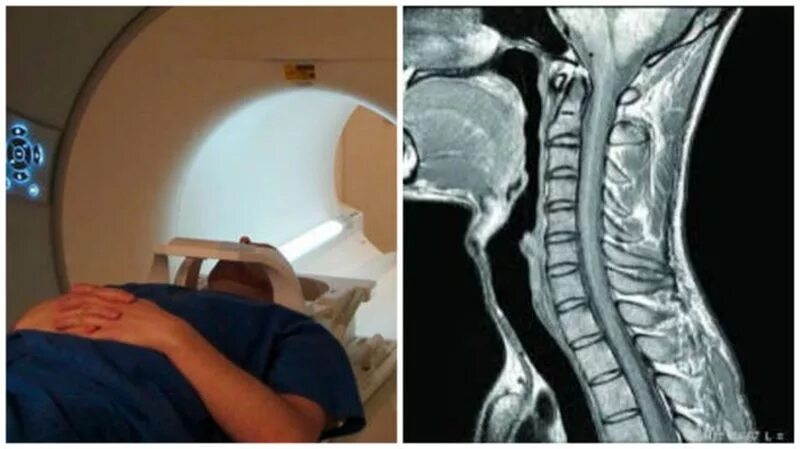

Сколько по времени делается мрт шейного отдела